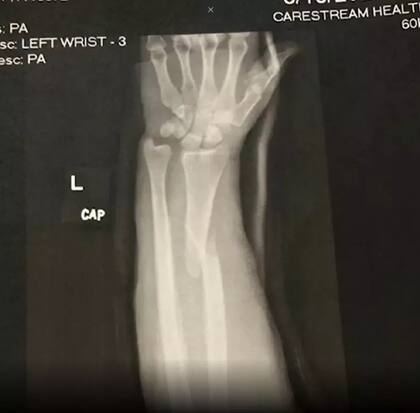

Ante la consulta sobre si sintió algún tipo de dolor en el momento de quebrarse, ella relató: “No. Probablemente debido a la adrenalina. Recuerdo que pensé que estaba viviendo un sueño. Me llevaron al hospital donde me hicieron radiografías y me dieron ibuprofeno. Resultó que me había roto el radio, un hueso que se ubica en el antebrazo”.

En ese marco, la mujer aclaró que ya encontró a más de diez personas haciendo la misma técnica que ella. “Nuestras historias y radiografías son idénticas, simplemente no publican sus videos porque es vergonzoso. Personalmente, no me importa”.

En cuanto a las versiones que indicaban que el problema no fue por el peso sino que por su densidad ósea, ella aclaró: “Mi cirujano dijo que mi densidad ósea está por encima del promedio, solo era mucha presión sobre un hueso pequeño”.

El hueso tardó un total de ocho semanas en curarse y le insertaron una placa junto a ocho tornillos en el brazo. Sin embargo, eso no impidió que Robyn volviera a las competiciones y estableció nuevos récords seis meses después de la operación.